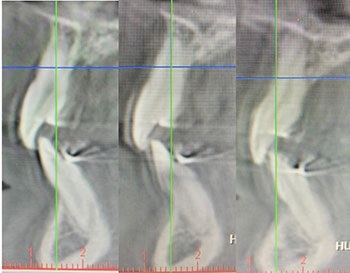

The previous case (Lea) and the lesson learned about how opening vertically will move the lower jaw not just down but also back were fresh in my mind. For Jolie, I understood that while opening her vertical would benefit her facial balance, it would also result in an even greater iatrogenic Class II occlusal burden. In the absence of orthognathic surgery (which was discussed with Jolie and her mother but declined) to move the mandible forward, attempting to non-surgically compensate for this problem by mesializing the lower dentition would seem to be an unwise decision, especially given the fact that Jolie showed a thin lower anterior periodontal phenotype with visible root scalloping (Fig. 2).

‘Short-Face’ Patients—Part 3

Fig. 2

The treatment plan I eventually chose was tailored to the very unique characteristics of her particular case—a short-face presentation paired with protrusive upper incisors and a slightly retrognathic mandible with associated Class II occlusion. Again, in the absence of surgery, my goal was to attempt to address both the significant vertical and A-P challenges as best as possible. Figure 2 is the start-day records.